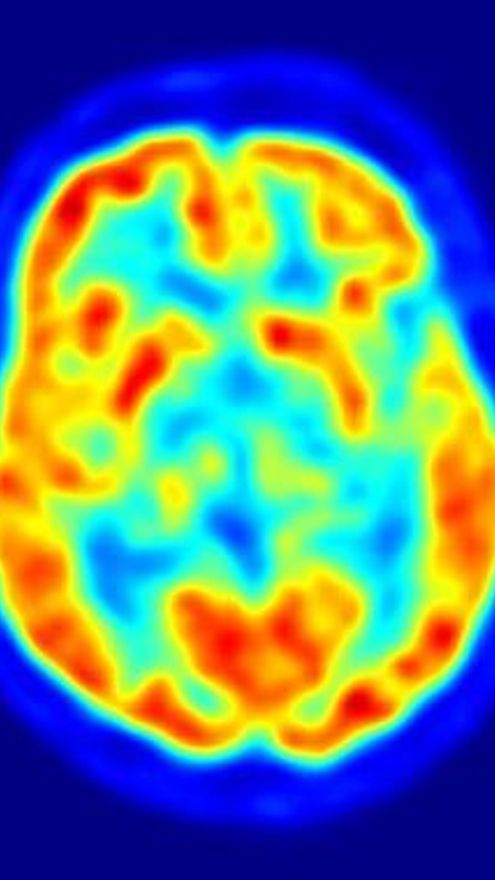

El banco de cerebros busca donantes, a ser posible enfermos de Parkinson

El banco de Tejidos de la Fundación Centro de Investigación de Enfermedades Neurológicas (CIEN), dependiente del Ministerio de Economía y Competitividad a través del Instituto de Salud Carlos III, necesita que aumente la donación de cerebros, principalmente de afectados por la enfermedad de Alzheimer y la enfermedad Parkinson, estos últimos especialmente difíciles de obtener.

La donación de cerebros es fundamental para poder estudiar las consecuencias de las enfermedades neurodegenerativas sobre el tejido humano. Desde la organización destacan que son “clave” y, por tanto, es “imprescindible” que aumenten las donaciones para avanzar en su investigación.

Por ello, la donación de cerebros es fundamental para poder estudiar las consecuencias de la enfermedad misma sobre el tejido humano, las cuales sirven además como contraste fundamental de los hallazgos experimentales. De hecho, de ellos depende el avance de la investigación.

“Uno de los objetivos primordiales de las investigaciones se centran en reconocer los cambios que se producen progresivamente en el cerebro de los individuos antes de que las enfermedades neurodegenerativas se manifiesten plenamente”, por lo que señalan se “hace muy necesario” contar con todo tipo de donantes de cerebro.

El BT-CIEN promueve el estudio de enfermedades neurológicas mediante el diagnóstico especializado y apoya la investigación neurocientífica en España. Para ello, su ámbito de actuación se centra en la recogida, procesamiento y almacenamiento de cerebros, sangre, líquido cefalorraquídeo y otros tejidos que hayan sido cedidos voluntariamente en vida.